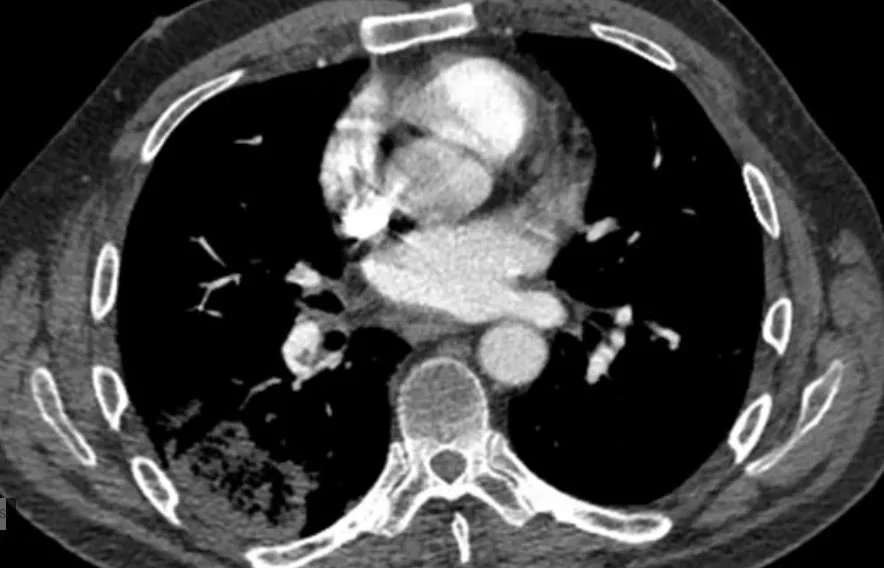

One of the findings on a non contrast CT that suggests a pulmonary infarct is the “bubble sign”  It is a highly specific marker for PE.   The necrotic lung shows areas of gas as in the image below.

the bubble sign of a pulmonary infarct